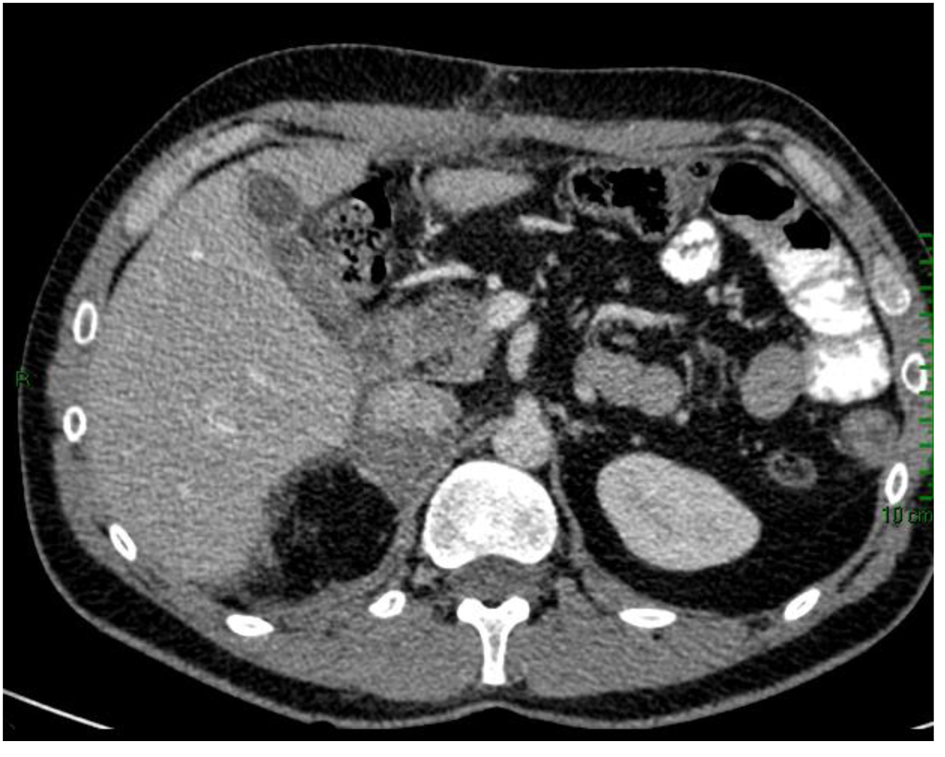

Subsequently, the patient was taken to the surgical oncology and had right radical adrenelectomy and total omentectomy. The final pathology report showed adrenocortical carcinoma, reaching surgical margins; vascular invasion; histological changes consistent with minor changes to neoadjuvant therapy; round stent without significant histological alterations; and YpT3NxM1 pathological staging. Post-surgical CT scan showed complete omentectomy and right adrenalectomy. However, an adrenal tissue around 7 × 3 cm which impresses tumor was observed. Visceral, peritoneal or bone metastatic lesions are discarded (Fig. 3).

![]() Click for large image | Figure 3. CT scan after surgical oncology showing right radical adrenalectomy and total omentectomy. |